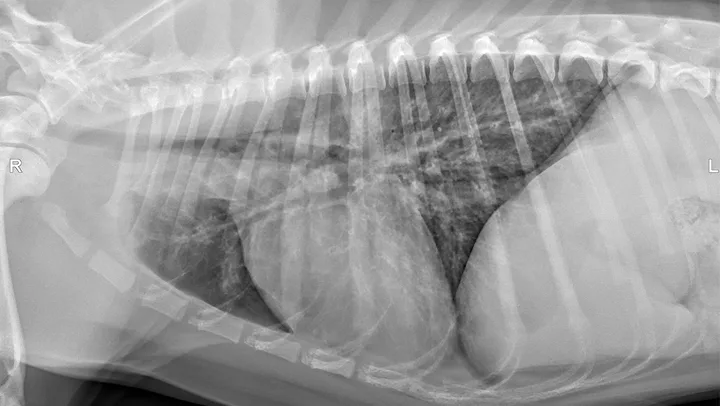

CDV should be suspected in poorly vaccinated dogs with multiorgan involvement. Dogs with CDV may have exhibited only respiratory signs before developing characteristic nonrespiratory signs.12 Radiographs may reveal a diffuse interstitial pattern (Figure 2). Diagnosis is supported by compatible clinical signs and complementary diagnostic testing (ie, real-time reverse transcription polymerase chain reaction [RT-PCR], serology, CSF pleocytosis). Conjunctival scraping and tissue-based immunohistochemistry may confirm diagnosis.

FIGURE 2

CDV pneumonia with a diffuse interstitial pattern confirmed by multisystemic signs, urine RT-PCR, and necropsy